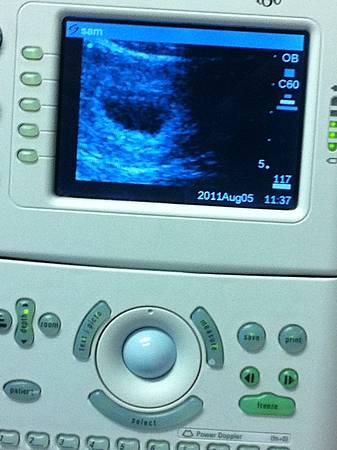

換好後沒多久,我的醫生就來了~這是第一次跟她相見歡,留著一頭俐落短髮有著親切笑容,頓時真是減少不少緊張氣氛~會找到這個醫生也是中獎後趕快求助這裡的朋友找到這位,她其實是台灣人在這長大,好處是會說中文,我自己覺得這樣比較好溝通,但今天P先生也在場,醫生當然很專業又尊敬的說大家都聽得懂的語言,於是就邊閒話家常聊邊取完抹片的採樣,還聊到台灣,整個就是很親切!之後就開始問我們有沒有什麼問題?就趕快把我們的清單拿出來一一詢問(明明書上都有寫,但人很奇怪就是要從醫生口中證實得到答案才會心安><),這些完之後重頭戲來了,醫生帶來了手提式的超音波器(這個好酷,在台灣看過大台的,這個我沒看過,小小的就拿在手裡,螢幕也小小的,像掌上型DVD),她幫我照了一下腹部,看到黑黑圓圓的一團在子宮內,據說這就是所謂的胚胎,我跟P兩個人對看了一下愣在那,好像沒什麼感覺啊??(這樣是正常的嗎??不是有人會喜極而泣??還是我們是怪人??)然後醫生說現在六週還太小,再隔兩星期再來照~我還在思考剛剛看的那小黑團就是我的baby?當然我知道還沒成形,但感覺得還是滿妙的,談不上興奮也不是奇怪,但就是一個字!!!!!然後趕快回到現實想說都沒有留下紀錄怎可?趕快問醫生可不可以讓照一下相,醫生很好還幫我們放大,P拿起我的iphone照下這張與baby初次見面的歷史性照片(這張歪了,另一張糊了,所以只好放歪的~由此可知,以後應該不用指望P先生可以幫我拍什麼紀錄了><),今天的見醫生經過大概是如此,兩個星期後再來囉!!!

31fc20.jpg